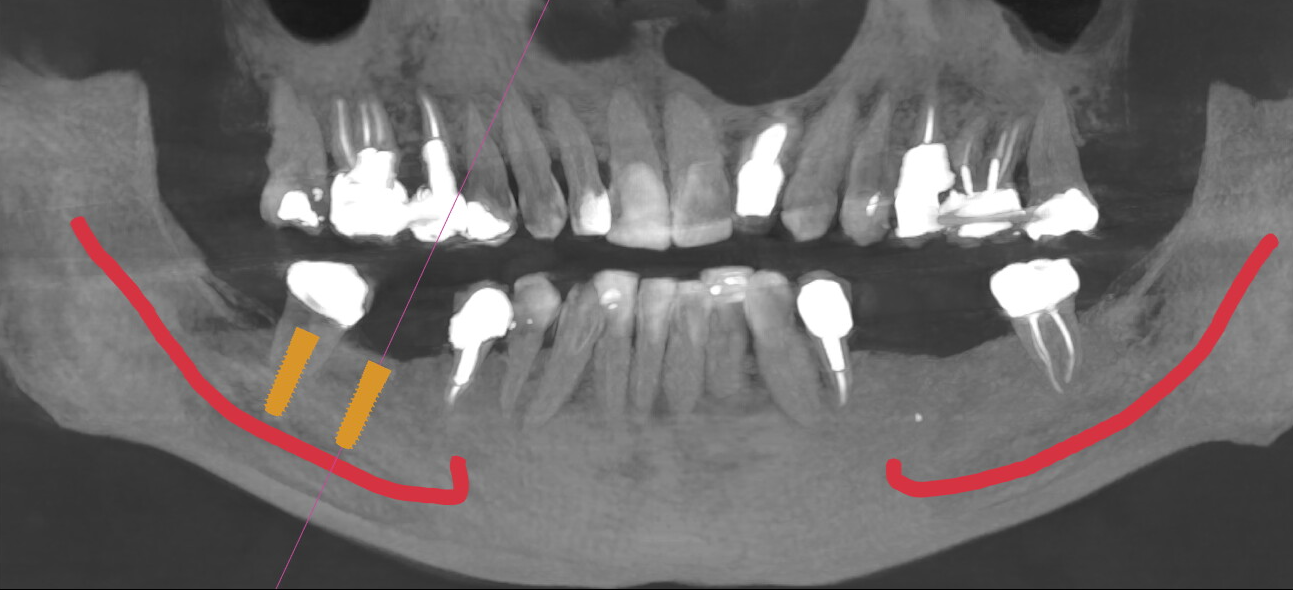

En implantologie, la précision n’est jamais abstraite : elle se mesure en millimètres et en degrés. Une déviation de 1 à 2 mm peut suffire à compromettre la stabilité d’un implant ou à mettre en danger une structure anatomique sensible. Longtemps, la radiographie 2D a constitué la base du diagnostic, malgré ses limites dès que l’anatomie se complexifie. Aujourd’hui, le cone beam dentaire (CBCT) s’impose comme bien plus qu’un examen d’imagerie : il est le pivot de la planification 3D et de la chirurgie guidée. En fournissant une vision tridimensionnelle fiable, il permet de passer d’une approche approximative à une chirurgie planifiée, mesurable et prédictible.

2. Enjeu clinique du cone beam dentaire en implantologie

L’imagerie 3D est aujourd’hui le standard en implantologie, car la radiographie 2D ne permet pas de mesurer avec précision. Les distorsions peuvent atteindre 20 à 30 %, rendant toute évaluation millimétrique incertaine.

Avec un CBCT, le praticien visualise précisément :

- le nerf alvéolaire inférieur,

- les sinus maxillaires,

- les foramens mentonniers et canaux accessoires,

- l’épaisseur réelle des corticales vestibulaires et linguales.

En pratique, une marge de sécurité de 2 mm par rapport au nerf alvéolaire est recommandée. Sans imagerie 3D, cette distance ne peut être garantie. Une erreur de positionnement de 1 à 2 mm peut suffire à provoquer une atteinte neurosensorielle ou une perforation sinusienne.

Le CBCT permet également une lecture qualitative de l’os : configuration trabéculaire, continuité corticale, volumes réellement exploitables. Ces éléments conditionnent directement la stabilité primaire et le pronostic implantaire.

L'apport majeur du cone beam dentaire réside dans son intégration au processus de planification implantaire. Il ne s’agit plus seulement d’observer, mais de concevoir l’acte chirurgical en amont, avec des paramètres chiffrés. La hauteur osseuse réelle permet de choisir une longueur implantaire (par exemple 8, 10 ou 12 mm), tandis que l’épaisseur disponible oriente le diamètre (3,5 mm ou 4,2 mm selon les cas). L’axe implantaire est défini de façon à éviter une déviation vestibulaire ou linguale de quelques degrés, parfois suffisante pour compromettre l’émergence prothétique.

Chirurgie guidée : précision en mm et en degrés

Les flux numériques issus du CBCT, associés aux empreintes optiques, ont fait émerger la chirurgie guidée. Les études rapportent des écarts moyens de l’ordre de ≈ 1 mm à l’entrée, ≈ 1–1,2 mm à l’apex, et une déviation angulaire autour de 3 à 4°. Ces chiffres, modestes en apparence, rappellent que chaque millimètre et chaque degré comptent. À l’inverse, la pose à main levée présente des variations plus importantes et une reproductibilité moindre, en particulier dans les zones anatomiquement contraintes.

La planification à partir du CBCT permet également d’anticiper les étapes complémentaires. Elle met en évidence la nécessité d’une greffe osseuse lorsque les volumes sont insuffisants, ou d’une élévation sinusienne (sinus lift) lorsque la hauteur sous-sinusienne est limitée. Ces décisions, prises en amont, sécurisent le geste et optimisent la cohérence prothétique du traitement.